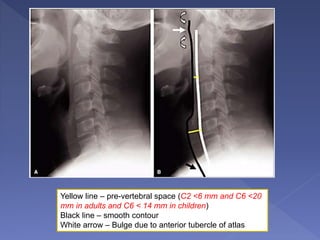

Yellow line – pre-vertebral space (C2 <6 mm and C6 <20

mm in adults and C6 < 14 mm in children)

Black line – smooth contour

White arrow – Bulge due to anterior tubercle of atlas